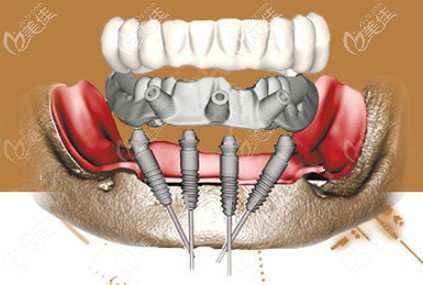

現(xiàn)在的全口種植牙無需28顆,基本上就是6-8顆就可以了,因此在選擇種植體材料上有了很多的空間,那要是選擇諾貝爾PCC種植牙一顆多少錢呢?

鄭州口腔種牙還挺靠譜,1年前做的Allon6現(xiàn)在吃東西依舊輕松 b588 G0 V0

其實做種植牙不怕花的錢多錢少,就怕的是花錢買罪受,比如術(shù)后基臺和種植體的密合性不好,長期如此引起能發(fā)炎疼痛。所以一定要找一家口碑好的醫(yī)院做種植,就像鄭州金水區(qū)的口腔,